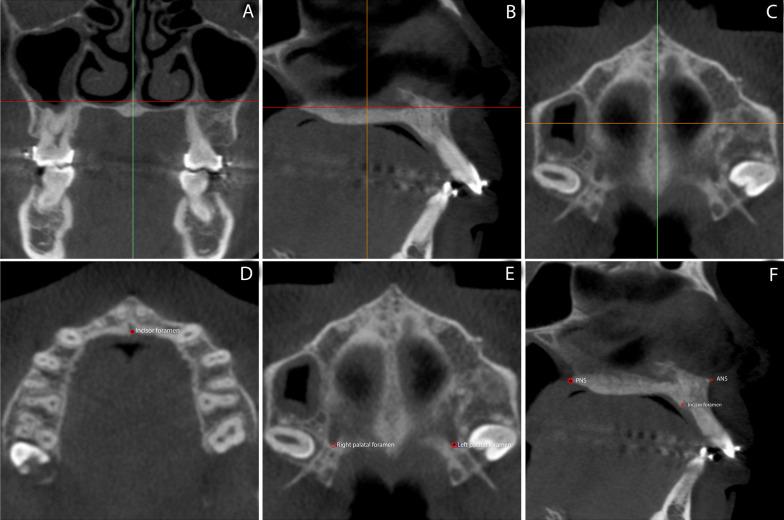

Forty-two patients aged 16-40 were recruited and randomly assigned into two groups, one which underwent MOPs (MOPG) in the buccal and palatal region of all maxillary incisors immediately before the start of retraction and one which did not (CG). Eligibility criteria included the orthodontic need for maxillary first premolars extraction and space closure in two phases. The primary outcome of the study consisted of measuring the rate of space closure and, consequently, the rate of incisors' retraction using digital model superimposition 14 days later and monthly thereafter for the next 4 months. The secondary outcomes included measuring anchorage loss, central incisors' inclination, and root length shortening, analyzed using cone beam computed tomography scans acquired before retraction and 4 months after retraction. Randomization was performed using QuickCalcs software. While clinical blinding was not possible, the image's examinator was blinded.

招募了 42 名年龄在 16-40 岁的患者,并将其随机分为两组,一组在开始内收前立即在所有上颌切牙的颊侧和腭侧进行 MOPs(MOPG),另一组不进行(CG)。入选标准包括上颌第一前磨牙拔牙和两期分阶段关闭间隙的正畸需求。研究的主要结果包括使用数字模型叠加测量 14 天后和随后每月测量 4 个月内的间隙关闭率,从而测量切牙的内收率。次要结果包括使用锥形束 CT 扫描测量支抗丢失、中切牙倾斜和根长缩短,在开始内收前和内收后 4 个月进行测量。随机化使用 QuickCalcs 软件进行。虽然无法进行临床盲法,但图像检查者是盲法的。